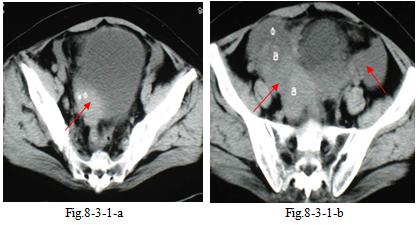

1.患者女性,76 岁。主诉:发现盆腔肿物 2 月余。妇科内诊:子宫萎缩,右附件区可扪及225px×200px 偏实性包块,压痛。CT 盆腔平扫(Fig.8-3-1-a~d)示:双附件囊实性恶性肿瘤,以囊性为主,与膀胱无 明确分界。右大网膜转移。右侧肿瘤自升结肠左侧向腹壁突出,使腹直肌边缘部分不清。手术:血性 腹水约300ml,双侧卵巢各有200px×150px×150px囊实性肿瘤,表面呈灰白色,网膜散在种植最大直径50px, 腹膜广泛种植,膀胱表面种植。术后病理:双侧卵巢多房性浆液性囊腺癌Ⅳ期(中分化),大网膜多处转移。